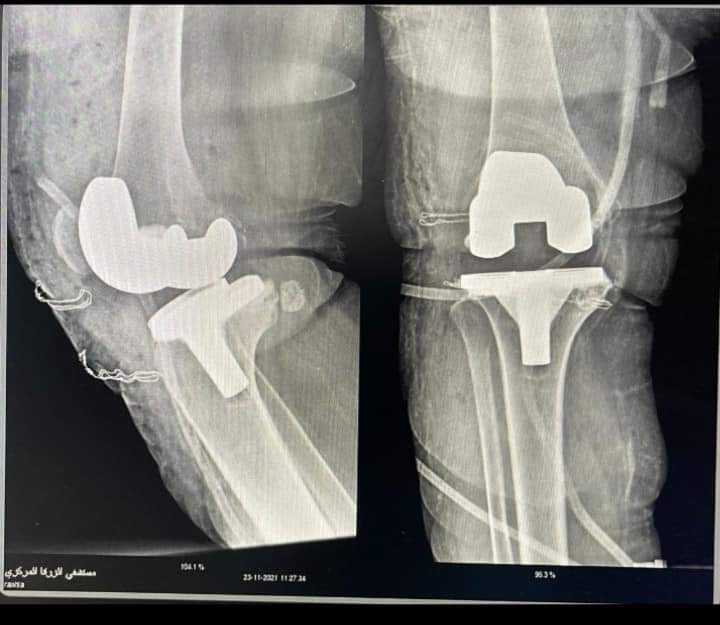

تركيب مفصل صناعي لمريض بمستشفي الزرقا المركزي

نجح أطباء مستشفى الزرقا المركزي بمحافظة دمياط بقيادة الدكتور عمرو شاهين، مدير المستشفي، من إجراء عملية تركيب مفصل صناعي لمريض بالمستشفي لأول مرة وذلك في ضوء توجيهات الدكتور السيد عبد الجواد، مدير مديرية الشئون الصحية والسكان بمحافظة دمياط، وبتضافر الجهود المبذولة من الدكتورة دعاء المحلاوي، مسؤول قوائم الإنتظار بمديرية الشئون الصحية والسكان بمحافظة دمياط.

وقال الدكتور عمرو شاهين، مدير مستشفي الزرقا المركزي بمحافظة دمياط، أن العملية الجراحية جاءت بمشاركة الفريق الطبي بقسم جراحات العظام والتخدير بالمستشفى لتركيب المفصل للمريض بعد أن كان يعاني من خشونة متقدمة في الركبة أدت إلى تشوه، لافتًا إلي أنه تم خروج المريض من المستشفى وهو بحالة صحية جيدة وقادر على الحركة.